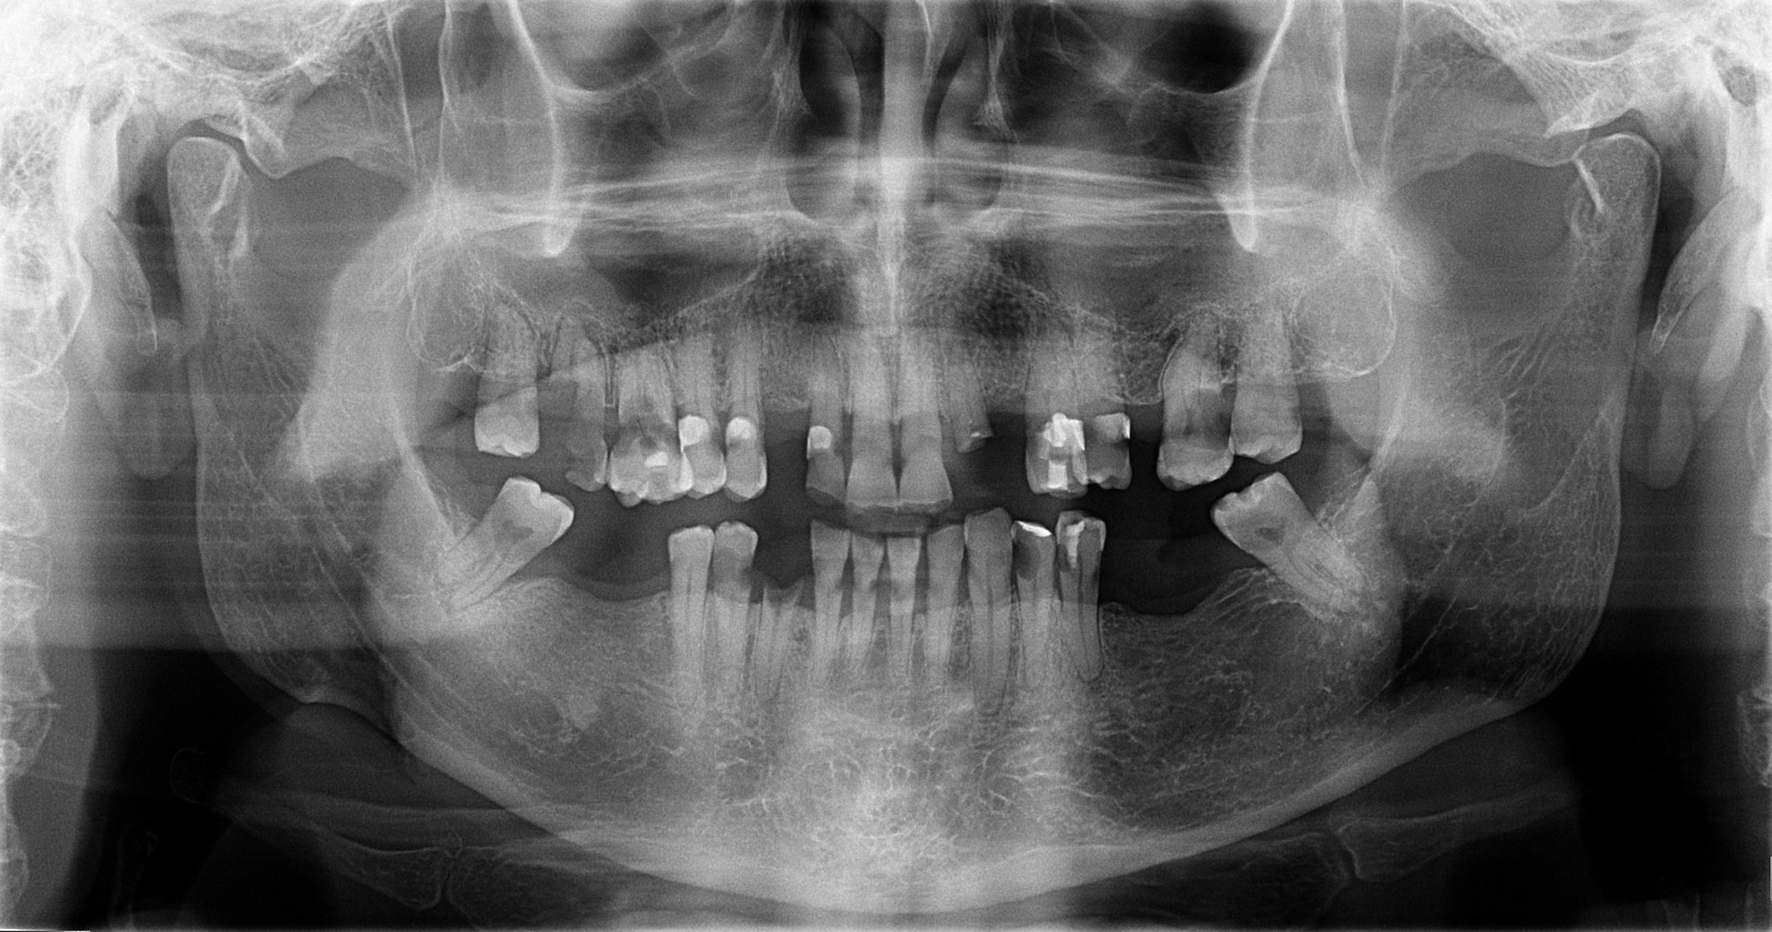

Osteoradionecrosis (ORN) is one of the most severe oral complications after the head and neck cancer treatment. Tooth extraction, through its traumatic stimulation, is identified as an important predisposing factor. Indications and preventive methods for carrying out these procedures in irradiated patients are questioned, thus, establishing appropriate protocols is essential. This article reports a case of multiple tooth extractions in a cancer patient whose preventive measures were taken without the occurrence of complications. Based on a literature review, this paper accounts the appropriate indications of this procedure, the risk of developing osteoradionecrosis, and the prevention possibilities for this sequela. In addition, this report addresses a viable oral rehabilitation alternative after this kind of surgery by using overdenture on the lower jaw teeth.